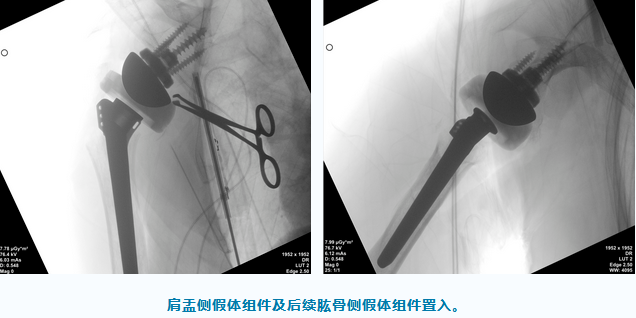

在导针的精准定位后,为患者置入肩盂侧假体组件,以及后续肱骨侧假体组件,顺利完成手术。手术共计耗时2小时,出血不到200ml,术后复查X片也显示假体植入位置非常满意。